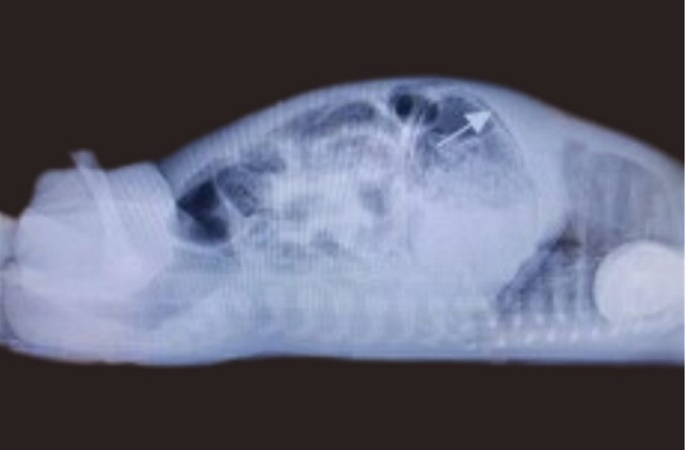

Bowel wall was notably thickened with air in the rectum. As gastric pneumatosis was a finding new to the managing team, intestinal perforation was initially considered; therefore a cross table lateral was requested, which confirmed gastric pneumatosis and pneumoperitoneum was ruled out, see Figure 2.Thrombocytopenia was noted. The lowest count observed was 70x103/uL (x109/L). Radiological and clinical findings therefore were in keeping with NEC stage 2a. He was re-screened and placed on Amoxicillin/Clavulanate potassium and Ceftazidime (second line as per local protocol) and Metronidazole was added.

Figure 2.Cross table lateral radiograph showing gastric pneumatosis (arrow shown)

Cross table lateral radiograph showing gastric pneumatosis (arrow shown)